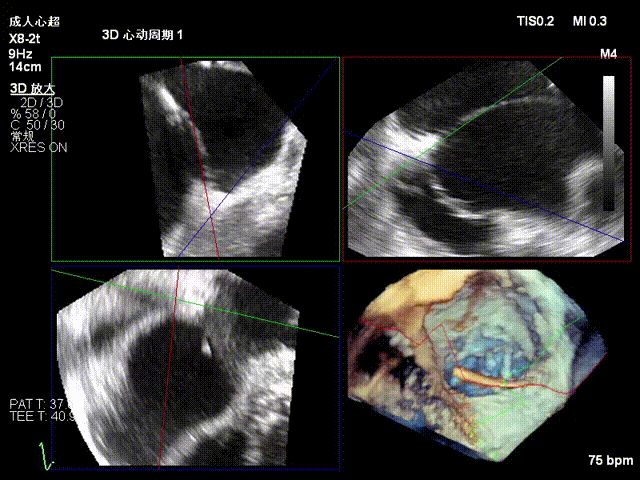

2.Annuloplasty Effect: Annular morphology remodeled, central gap significantly reduced.

Preoperative 3D

Postoperative 3D